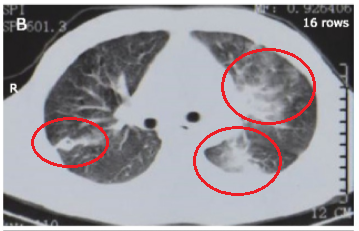

(第二次胸部CT)

一抗就是3年。

这期间患者还是有各种各样的不舒服,胃口不好,吃东西不多,觉得腹胀,乏力,胸口不舒服。时间长了,人也变得消瘦了。一看就是一个重病缠身的样子。

直到2018年,患者去了一家省级三甲医院,医生看完情况后也觉得很奇怪,于是安排重新做了一次胸部增强CT,并且做了三维重建。

也正是由于这个竹签一直留在胸腔、肺内,所以彩会导致反反复复的感染,反复炎症,也有脓肿形成,从三维重建来看,竹签直接刺入了左肺动脉,时间长了就会影响了右心脏,导致右心符合增高,继而出现右心衰竭。所以患者会有胃肠道淤血表现,有胃口不好、腹胀等。

苦命的是,患者还一直被当做肺结核来治疗,还坚持了3年的抗结核治疗。

当然,这三年的抗结核治疗效果是不好的。

当初医生为什么误诊为肺结核呢?除了症状像,更重要的是胸部CT表现也像。我们说原发型肺结核的X线胸片表现为哑铃型阴影,哑铃大家见过吧?就是原发病灶、肿大的肺门淋巴结这两个看起来像哑铃的两端,而中间的引流淋巴管炎像哑铃中间那根铁(手握住的地方),就好像这样:

然后这个患者的表现也是符合的,因为竹签啊,这根竹签模拟了引流淋巴管炎的情况,两端还有脓肿病灶,看起来真的很像原发型肺结核,所以为什么几家医院都会以为是肺结核。